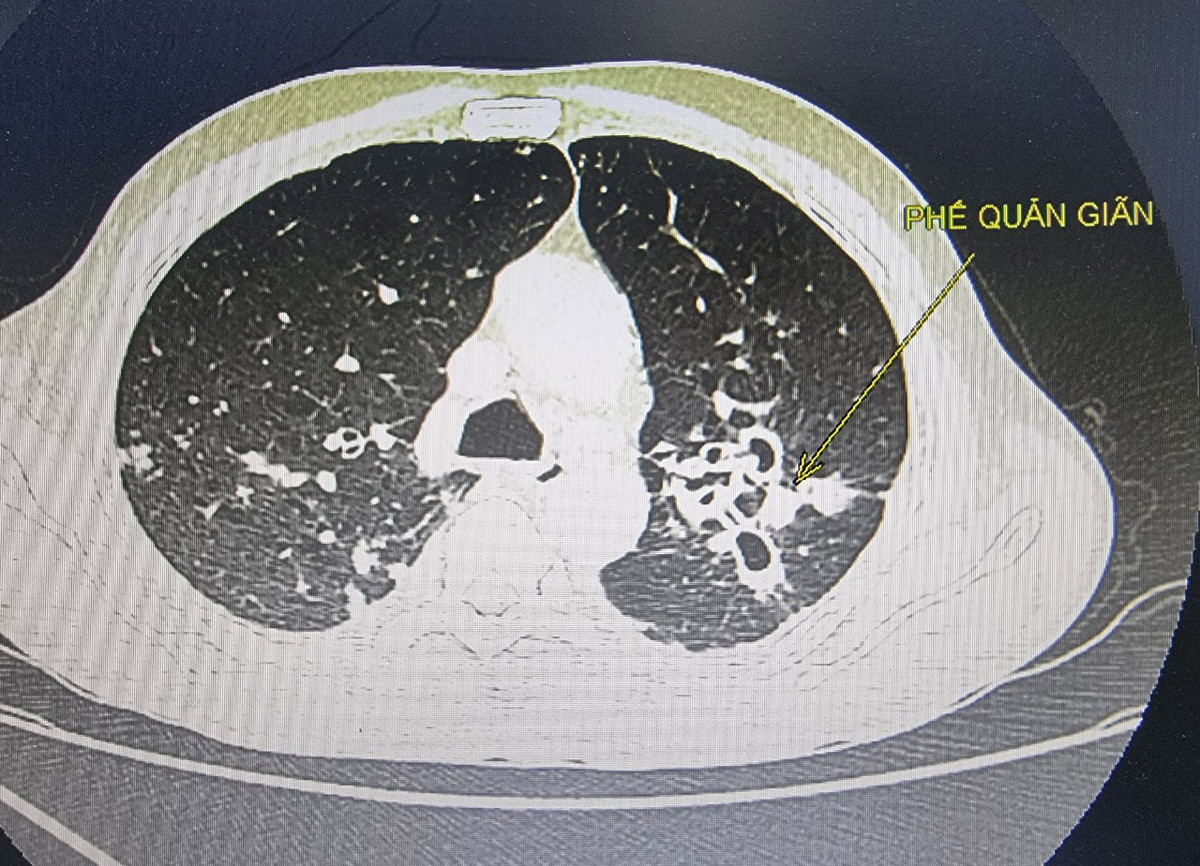

Rất hiếm khi ho dai dẳng, kéo dài lại là dấu hiệu cảnh báo ung thư, thường các dấu hiệu này là do chảy dịch sau mũi, hen suyễn, trào ngược thực quản, nhiễm trùng... Nhưng nếu sau khi được điều trị mà bệnh không thuyên giảm hoặc ho ra máu, nhất là khi bạn không phải là người hút thuốc lá thì nên đến gặp bác sĩ, có thể bạn sẽ được cấy đờm hoặc làm các xét nghiệm, chụp chiếu… cận lâm sàng để rà soát ung thư phổi.